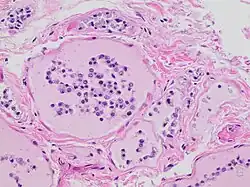

Autolysis is uncommon in living adult organisms and usually occurs in necrotic tissue as enzymes act on components of the cell that would not normally serve as substrates. These enzymes are released due to the cessation of active processes in the cell that provide substrates in healthy, living tissue; autolysis in itself is not an active process. In other words, though autolysis resembles the active process of digestion of nutrients by live cells, the dead cells are not actively digesting themselves as is often claimed, and as the synonym self-digestion suggests. Failure of respiration and subsequent failure of oxidative phosphorylation is the trigger of the autolytic process.[1] The reduced availability and subsequent absence of high-energy molecules that are required to maintain the integrity of the cell and maintain homeostasis causes significant changes in the biochemical operation of the cell.

Limited synthesis of adenosine triphosphate impairs many cellular transport mechanisms that utilize ATP to drive energetically unfavorable processes that transport ions and molecules across the cellular membrane. For example, the membrane potential of the cell is maintained by the sodium-potassium ATPase pump. Failure of the pump results in loss of membrane potential as sodium ions accumulate within the cell and potassium ions are lost through ion channels. Loss of membrane potential encourages movement of calcium ions into the cell, followed by movement of water into the cell, as driven by osmotic pressure.[3] Water retention, ionic changes, and acidification of the cell damages membrane-bound intracellular structures including the lysosome and peroxisome.[1]

Lysosomes are membrane-bound organelles that typically contain a broad spectrum of enzymes capable of hydrolytic deconstruction of polysaccharides, proteins, nucleic acids, lipids, phosphoric acyl esters, and sulfates. This process requires compartmentalization and segregation of enzymes and substrates via a single intracellular membrane that prevents unwarranted destruction of other intracellular components. Under normal conditions, the molecular machinery of the cell is further protected from lysosomal enzyme activity by regulation of cytosolic pH. The activity of lysosomal hydrolases is optimal at a moderately acidic pH of 5, which is significantly more acidic than the more basic average pH of 7.2 in the surrounding cytosol.[1] However, the accumulation of products of glycolysis decreases the pH of the cell, reducing this protective effect. Furthermore, lysosomal membranes damaged by water retention in the cell will release lysosomal enzymes into the cytosol. These enzymes are likely to be active due to the decreased cytosolic pH and are thus free to utilize cellular components as substrates.[1]

Peroxisomes typically are responsible for the breakdown of lipids, particularly long-chain fatty acids. In the absence of an active electron transport chain and associated cellular processes, there is no metabolic partner for the reducing equivalents in the breakdown of lipids.[1] In terms of autolysis, peroxisomes provide catabolic potential for fatty acids and reactive oxygen species, which are released into the cytosol as the peroxisomal membrane is damaged by water retention and digestion by other catabolic enzymes.[1]